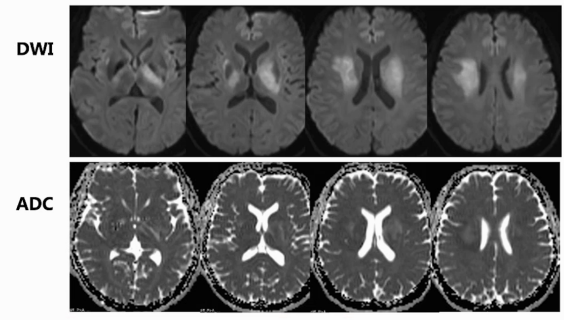

颅脑磁共振:双侧基底节区、放射冠区域片状长T2高信号,累积部位深,无显著占位效应,呈长T1长T2信号。增强后,仅见小斑片状轻度强化影,左侧基底节区及放射冠区域较明显,脑岛区无明显异常强化。DWI信号增高,部分区域ADC信号减低,提示弥散受限。多体素MR波谱扫描多数区域胆碱峰升高,部分体素N - 乙酰天门冬氨酸峰降低。SWI和颅脑MRA扫描未见明显微出血及血管异常。颅脑灌注加权成像显示病灶区域脑血流量CBF、脑血容量CBV轻度升高,达峰时间TTP及平均通过时间MTT稍延迟。